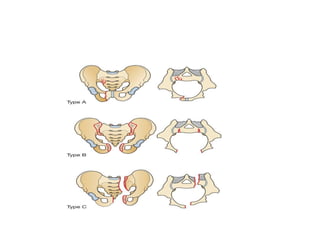

• Classification

➢Pelvic ring fractures can be classified into three

types, However, no fracture pattern can exclude

significant haemorrhage.

❖Type A

✓Type A are the most common fractures and are

completely stable. They result from lateral

compression, which causes compression fractures

of the pubic rami or compression fracture of the

sacrum posteriorly.

❖ Type B

✓ These fractures are partially stable, and there is disruption of the

anterior pelvis and partial disruption of the posterior pelvis. The

pelvis can open and close ‘like a book’, but because the sacroiliac

ligaments remain intact there is no vertical displacement. Internal

or external stabilization is required. Blood loss can be significant.

❖ Type C

✓ This fracture is completely unstable. Both the anterior pelvis and

the entire posterior pelvic complexes are disrupted and the

disrupted pelvic bones are free to displace horizontally and

vertically.

❑ In both type B and type C pelvic injuries, there is a high risk of

associated abdominal injuries (bowel perforation or mesenteric

laceration) and rupture of the diaphragm.